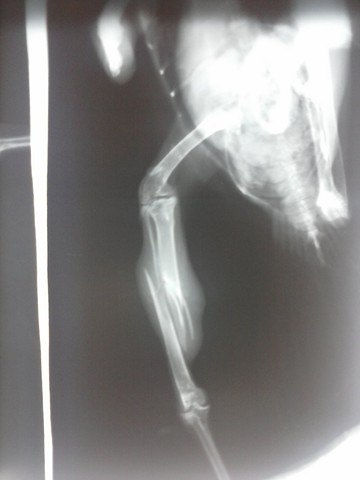

• У вороши перелом берцовой кости со смещением.

Сделан рентген в ЦВК, показана операция остеосинтеза.

26.06.12г. проведена операция, прогноз осторожный.

• Птишк уже после операции - на снимке видно внешнюю